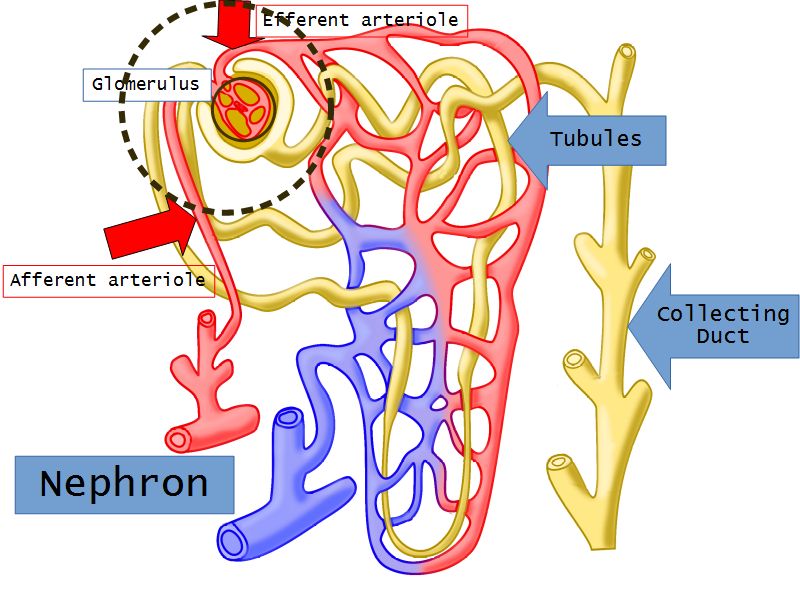

Nephron

- Unit responsible for

- Filtration

- Excretion

- Resorption

- Include

- Kidney tubule

- Glomerulus

- Exclude

- Collecting tubule

Nephron

- Renal corpuscle

- Proximal convoluted segment

- Long loop of Henle

- Descending portion

- Ascending portion

- Distal convoluted segment

Blood flow

- Efferent arteriole

- Smooth muscle in media

- Capillaries

- Fenestrated

- Afferent arteriole

- Smooth muscle in media